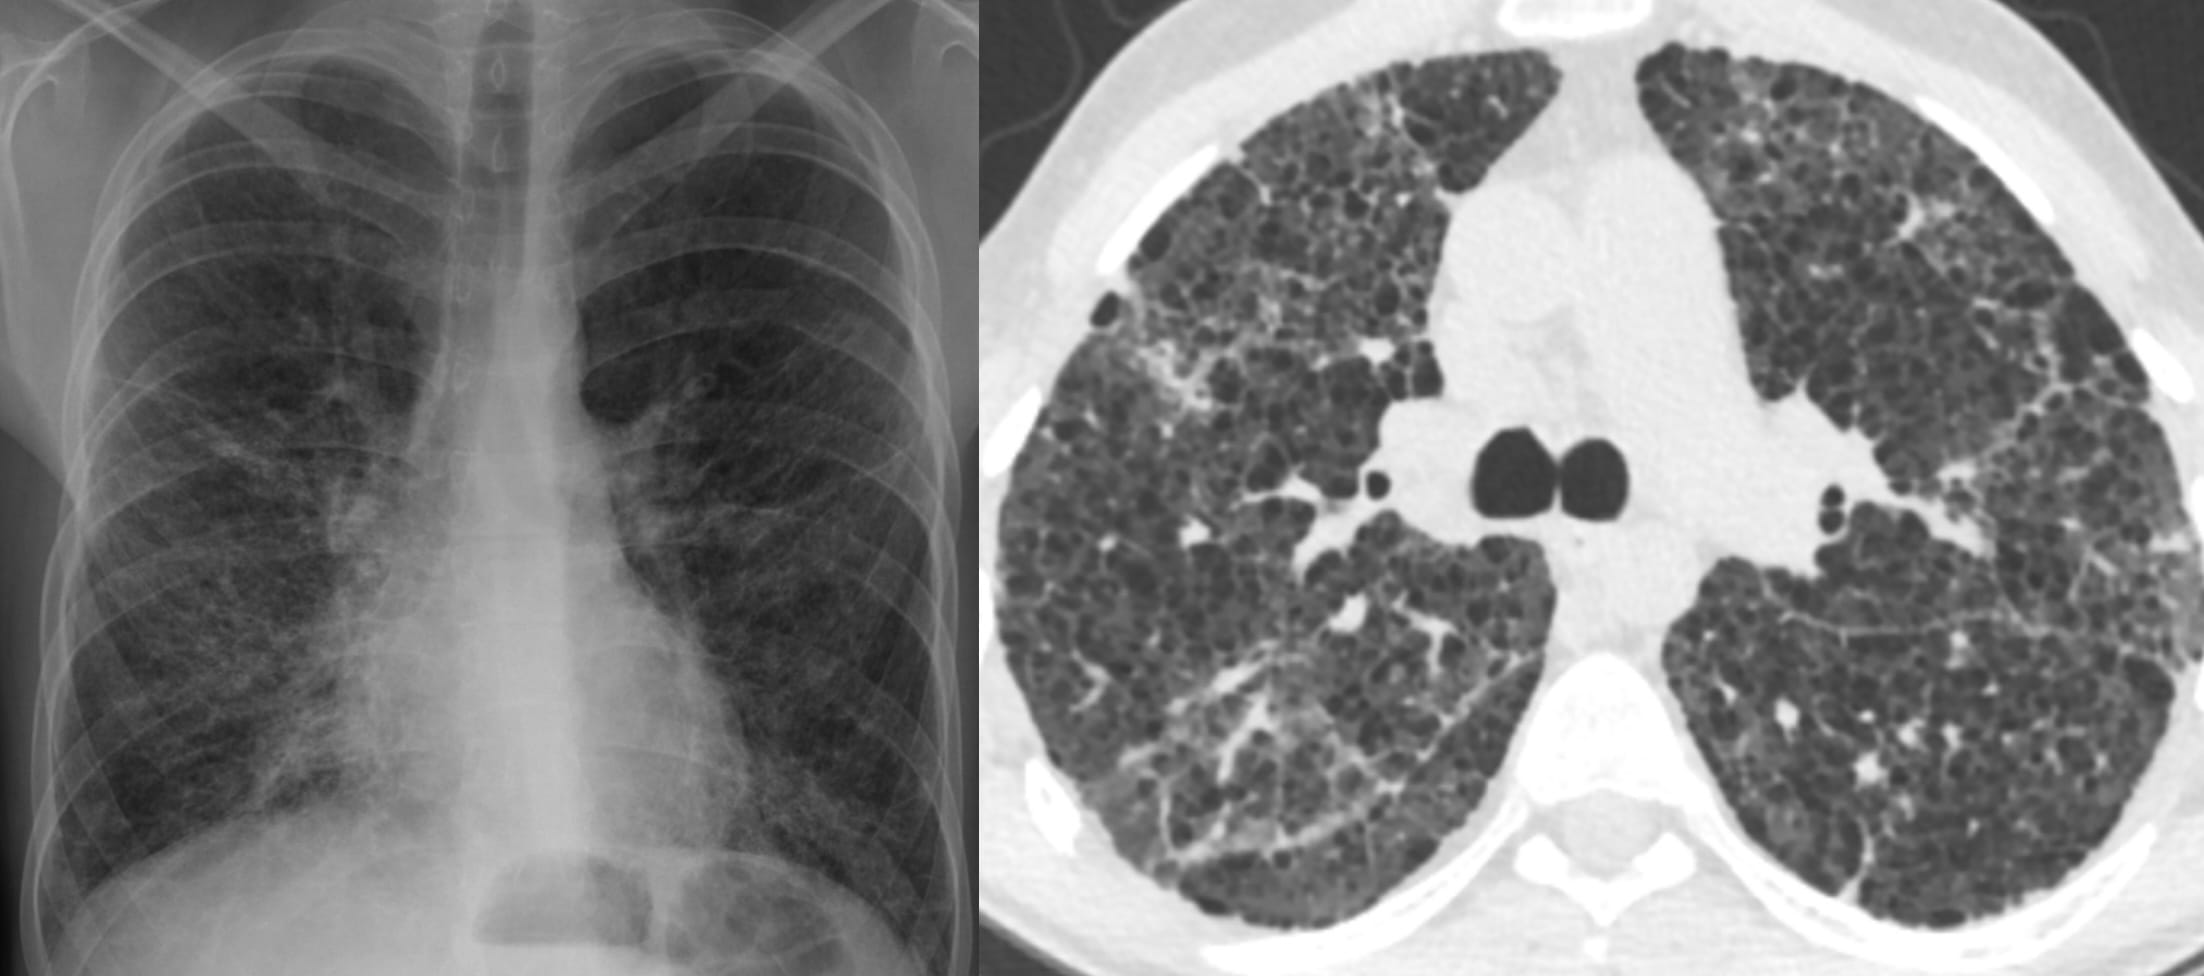

- Interstitial Lung Abnormalities